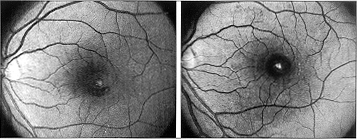

2周后,左眼症状性暗点仍存在,最佳矫正视力为20/70。左眼眼底检查显示黄斑下出血已吸收,但直径350μm的全层黄斑孔仍存在,孔底部的视网膜色素上皮和玻璃膜上可见激光损伤的黄色褪变,孔周视网膜下液呈袖状分布,视网膜轻微隆起,伴有早期黄斑前膜形成(图1,左)。荧光素血管造影显示中央部“窗样”缺损性高荧光。

图1 左,26岁男性患者左眼钛-蓝宝石激光意外损伤后2周,眼底检查显示黄斑下出血吸收,直径350μm的黄斑孔持续存在。孔底部的视网膜色素上皮和玻璃膜上见激光损伤所致的黄色褪变。孔周视网膜下液呈袖状分布,局部视网膜轻度隆起,孔下方见少量残留的视网膜下出血。右,术后6个月,黄斑孔保持封闭,激光对视网膜色素上皮和玻璃膜的残留损害明显可见

对患者进行了扁平部玻璃体切割术,术中用一种带弹性软头的笛针剥离玻璃体后皮质,剥除早期的视网膜前膜,然后行气液交换,最后填充15%过氟丙烷,保持面朝下的姿势3周。术后6周,患者发现暗点明显减小,只局限在中央区周围的鼻侧(图2),视力为20/30,黄斑孔封闭,周围的视网膜与其下方的视网膜色素上皮附着良好,残留的视网膜色素上皮和玻璃膜的激光损害位于旁中心小凹的颞侧,直径约150μm(图1,右)。